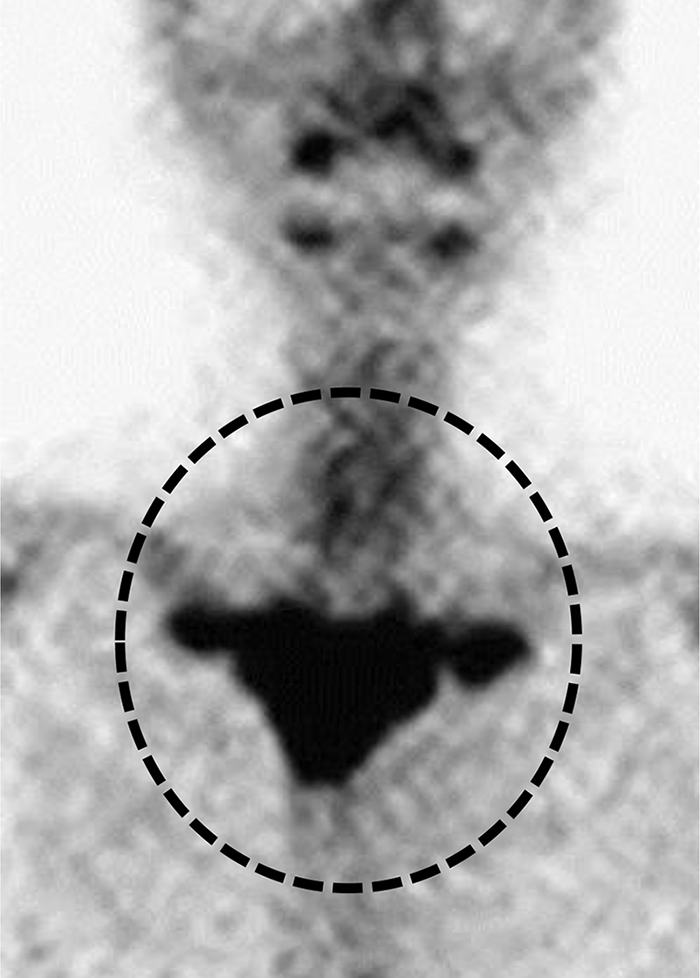

Fratture sacrali da insufficienza in una donna di 82 anni con osteoporosi e lombalgia cronica.

La scintigrafia ossea in proiezione posteriore mirata alla pelvi, evidenzia una netta e simmetrica ipercaptazione a livello dell’osso sacro. Il radiotracciante si distribuisce lungo due bande verticali (corrispondenti alle ali sacrali fratturate) unite da una banda orizzontale trasversale (corrispondente al promontorio sacrale). Questa morfologia ad “H”, che ricorda il logo della nota casa automobilistica, segno di “Honda” (Honda sign) è un segno classico e altamente specifico per questo tipo di lesione.

La TC con ricostruzione coronale conferma visivamente il danno strutturale, mostrando le evidenti rime di frattura verticali a carico del sacro indebolito.

Le fratture da insufficienza si verificano quando uno stress meccanico normale (fisiologico) viene applicato a un osso con resistenza elastica o contenuto minerale ridotti (come nell’osteoporosi grave). Il sacro è una delle sedi più tipiche, e la scintigrafia ossea è estremamente sensibile nell’individuarle anche quando le radiografie tradizionali risultano negative.